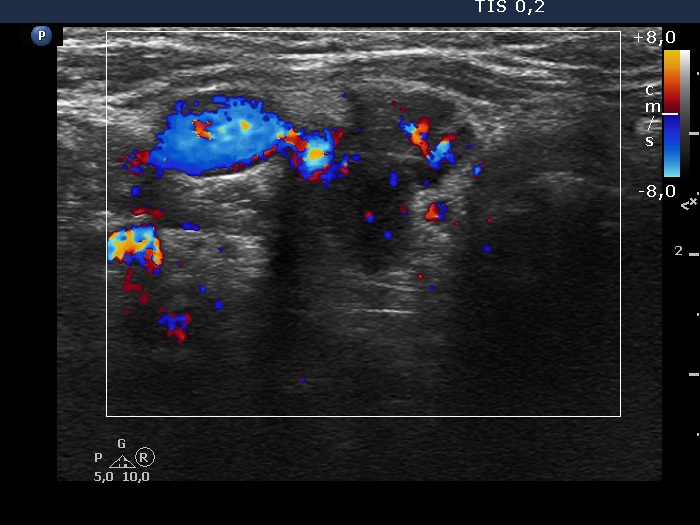

The echogenicity of the nodule - case 2121 (ultrasonographic picture 7)

Lower part of the right lobe, transverse scan, color Doppler mode. The hypoechoic lesion has irregularly increased intranodular vascularization.